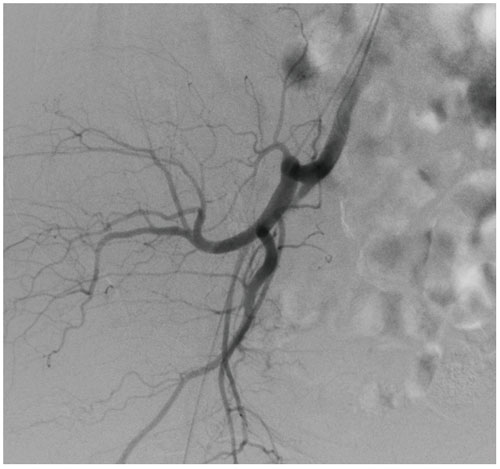

• DSA: DSA is used to clearly visualize blood vessels in a

bony or dense soft tissue environment. Images are produced using contrast medium by subtracting a “pre-contrast image” or mask image from subsequent images, once the contrast medium has been introduced into a structure.

High-quality image chains Ultra-clear images:

• 12-inch dynamic FPD: Large dynamic FPD with smaller pixel size, ensuring distortionless imaging; Wider FOV, avoiding overlapping and omissions, reducing exposure time and radiation dose, and shortening the operation time.